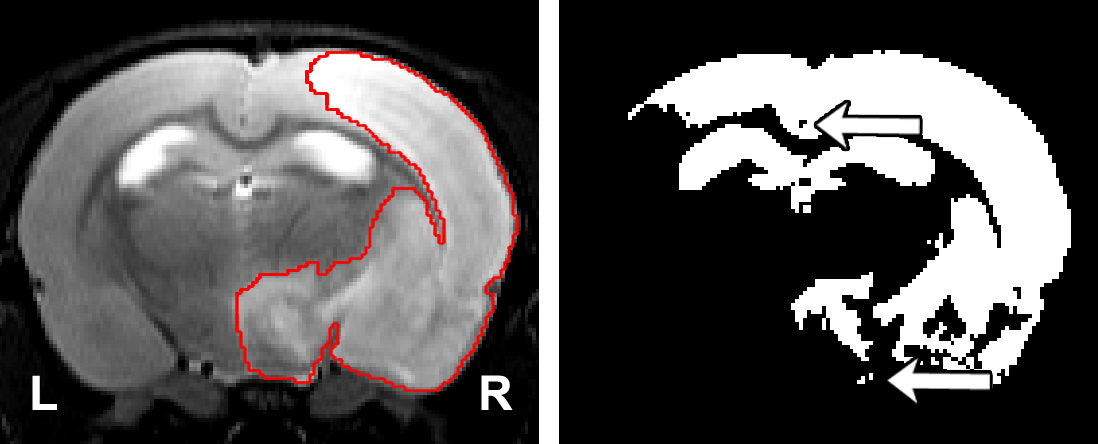

Refer to caption

Figure 1: Left: Representative lesion with its ground truth. Right: Segmentation of the lesion using thresholding where the threshold was found by maximizing the Dice coefficient with respect to the manual segmentation. The arrows indicate the presence of holes and islands (independently connected components) within and outside the mask, respectively. The hippocampus and ventricles were entirely misclassified as lesion.

Semi-automatic methods are a faster alternative to manual segmentation. However, they fail to overcome the subjectivity of the manual segmentation, as human interaction is required. To the best of the authors’ knowledge, there are only two studies that introduce and evaluate semi-automatic algorithms for rodent brain lesion segmentation. [7] evaluated a combination of thresholding operations commonly used in the literature to segment lesions on apparent diffusion coefficient (ADC) maps and T2-weighted images. [8] first normalized the intensity values of each image with respect to the contralateral hemisphere of the brain, and they performed a series of thresholding operations to segment permanent middle cerebral artery occlusion ischemic lesions in 31 diffusion-weighted images (DWIs) of the rat brain. Both methods require the manual segmentation of the contralateral hemisphere. Additionally, these thresholding-based and other voxel-wise approaches disregard the spatial and contextual information of the images, and they are sensitive to the image modality, contrast, and possible artifacts. Pipelines that rely on thresholding operations may result in poor and inconsistent segmentation results in the form of holes within and outside the lesion mask (Fig. 1).

Since our model optimizes a per-voxel loss function, small undesirable clusters of voxels may appear disconnected from the main predicted mask. These spurious clusters may be referred as “islands” when they are separated from the largest connected component and “holes” when they are inside the lesion mask. Figure 1 illustrates these terms.